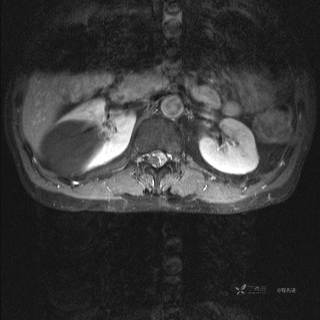

MR

T2

T2压脂

T1

T1增强

T1增强冠状位

T1增强横断位